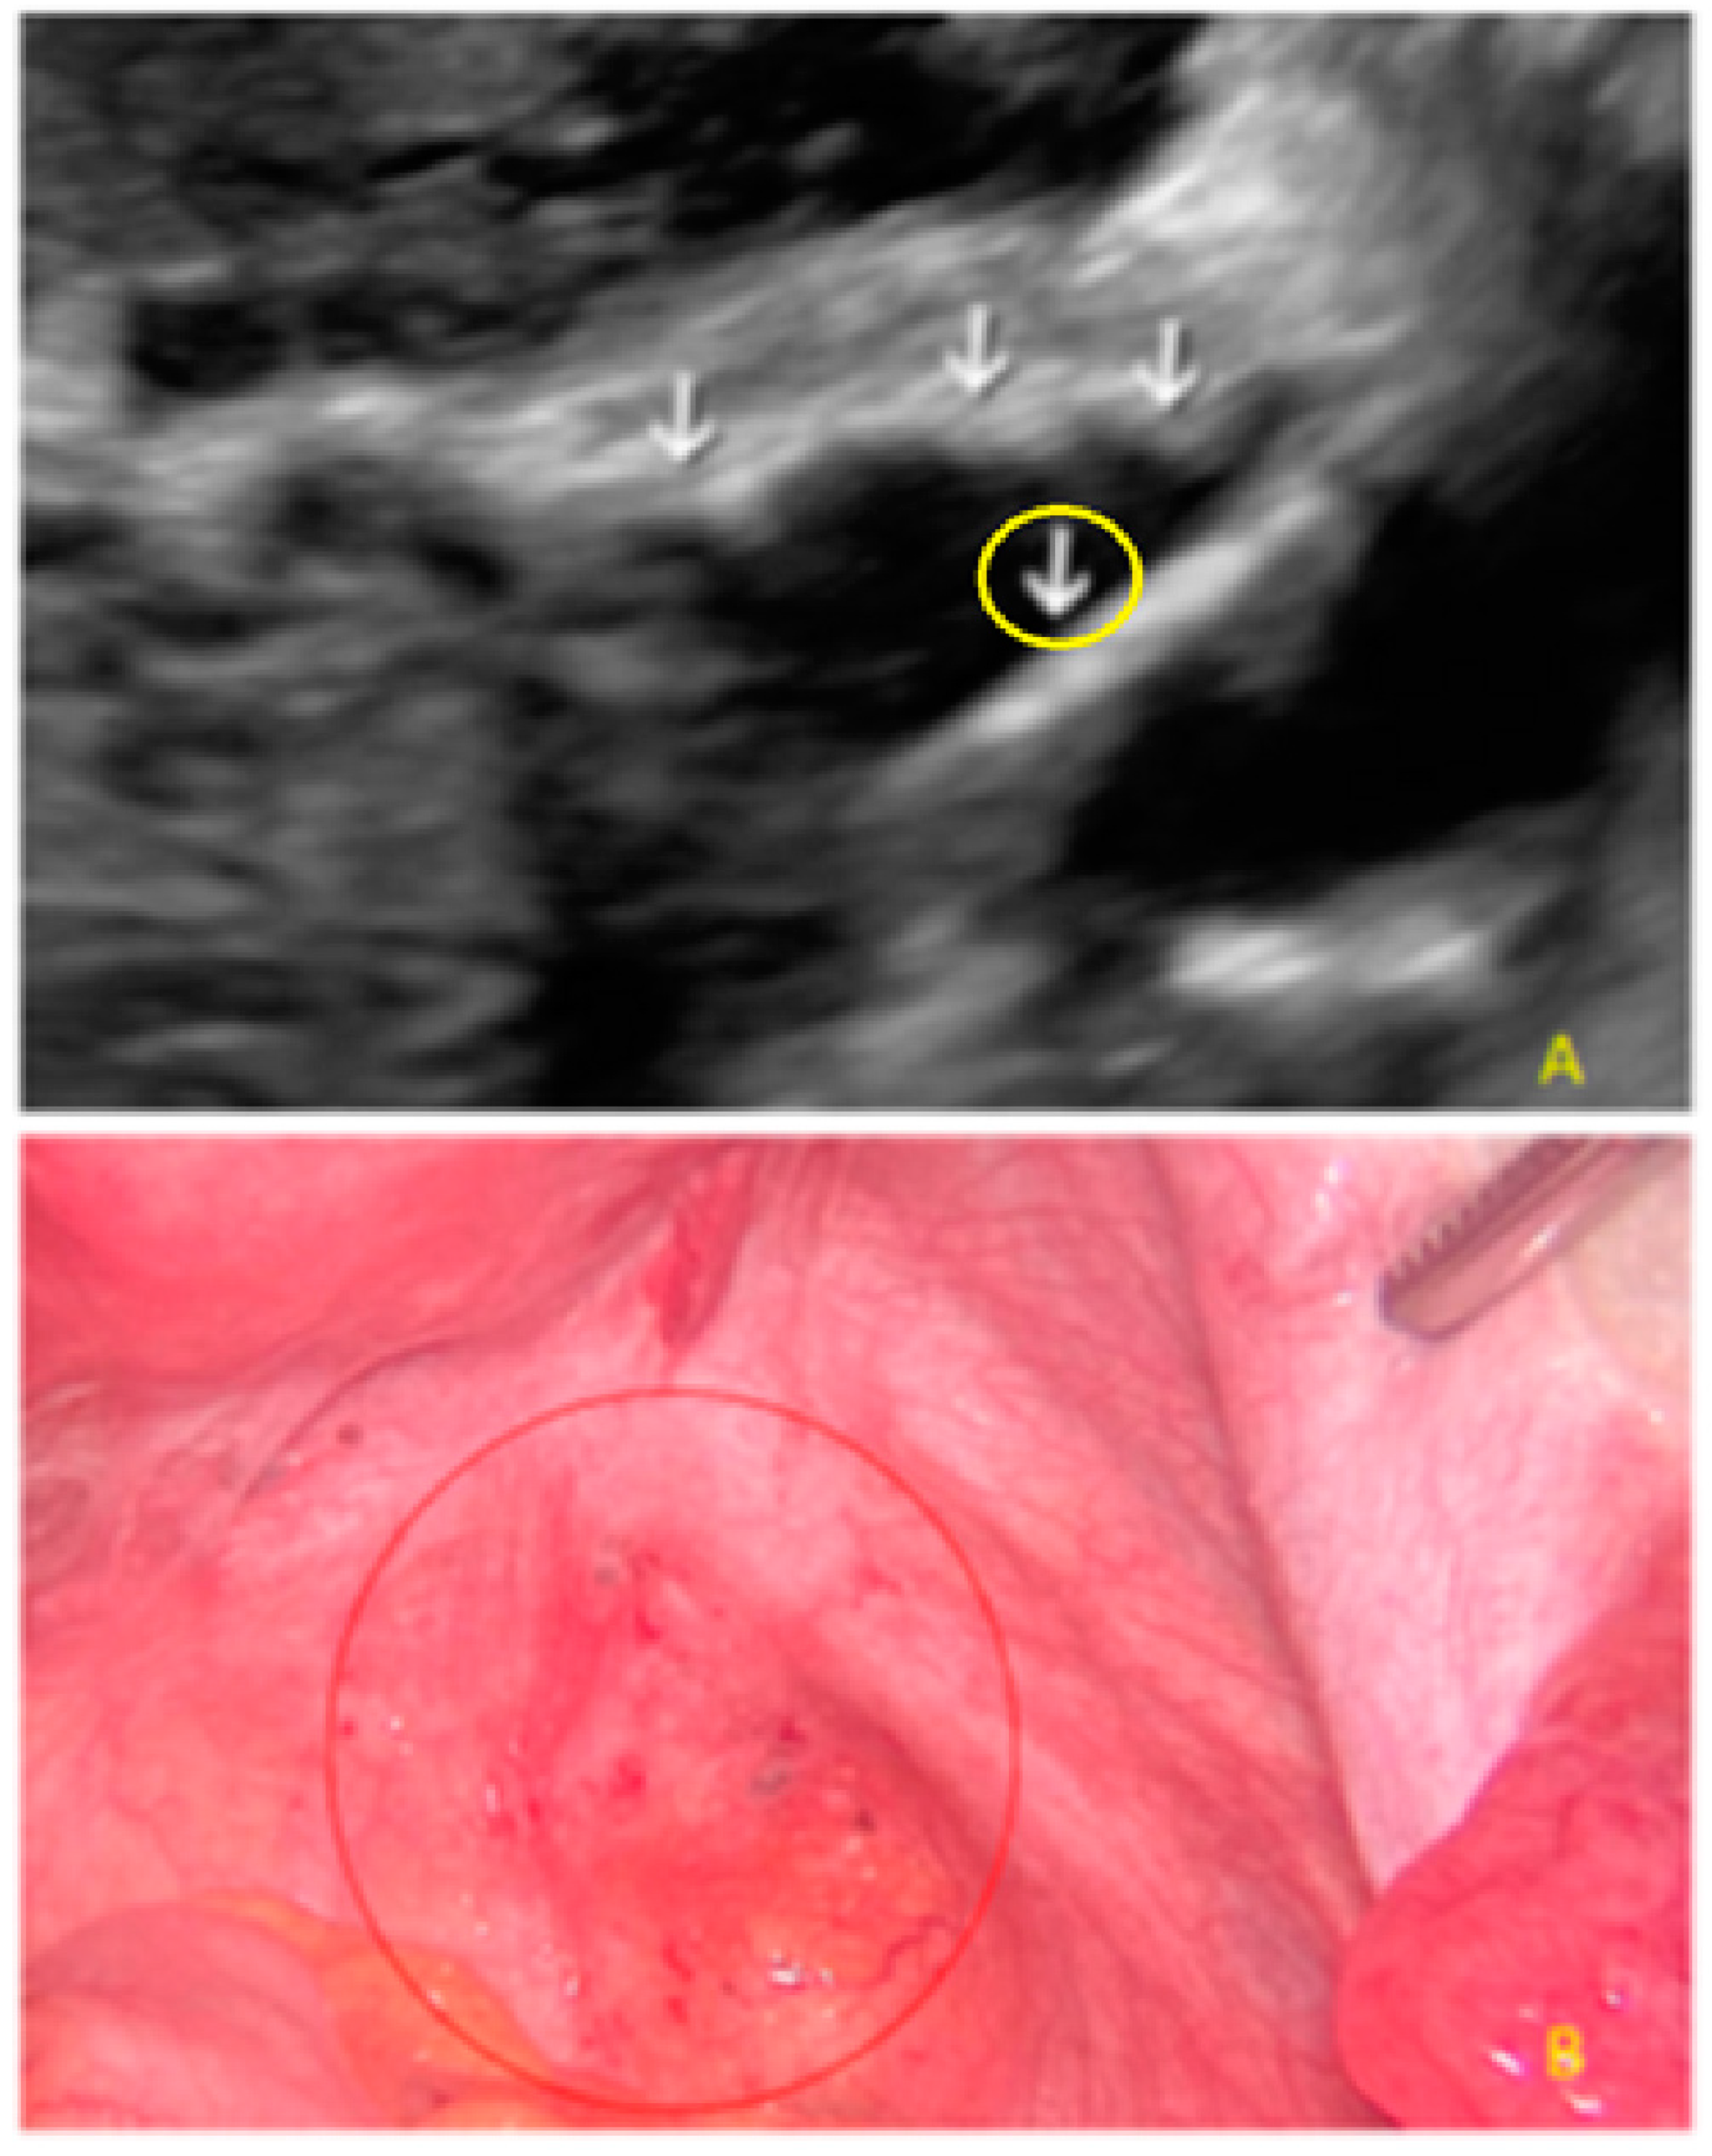

- The presence of hypoechogenic associated tissue (hypoechoic areas surrounding a small cyst area; we called this a “hat”). This tissue does not protrude or invaginate the peritoneal surface.

- The lesion may be convex, protruding from the peritoneal surface into the peritoneal cavity (we called this “bulging”), or it may appear as a concave defect in the peritoneum (we called this a “pocket”).

- The presence of velamentous (filmy) adhesions associated to the lesion (we called this a “veil”).